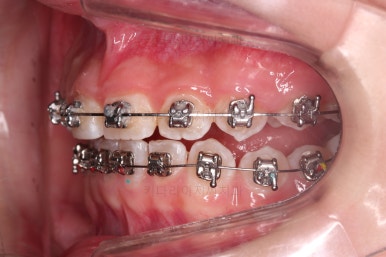

아랫니도 바로 교정장치를 부착하고, 교정장치를 통해 윗니와 아랫니를 끌어주고 철사를 이리저리 디자인해서 힘을 주고, 다양한 부가적인 부착물들을 활용하기로 했어요.

어떤 장치가 중간중간 활용되고 있는지는 틀린그림찾기처럼 찾아보시길 바랍니다😄

과개교합, 옥니, 앵글씨 2급 부정교합 모두 좋아지고 있어요.

마무리를 해줍니다.

앞니 각도가 매우 좋아졌고요.(옥니 개선) 위아래 앞니가 덮는 정도도 개선이 되었어요.(과개교합, 딥바이트)

엉성했던 어금니 맞물림도 매우 좋아졌어요.(앵글씨 2급 부정교합 개선)